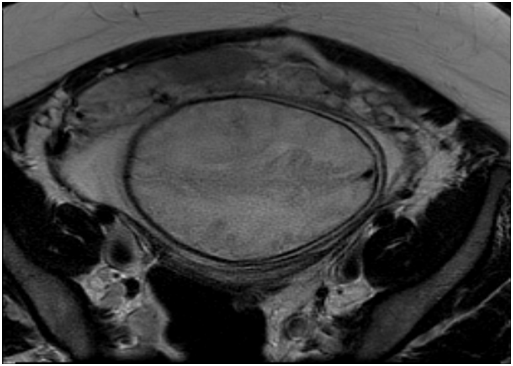

A 31-year-old woman (gravida VI, para III) with no concomitant diseases and a history of prior cesarean section due to placenta previa. During pregnancy was made regular 1st and 2nd trimester ultrasonography to rule out fetal pathology and a low-lying or adherent placenta, but the scan did not show any signs of an abnormal placenta or other problems. On admission 13.06.2016 at 3:15am, the patient presented frequent voiding of urine and pulling abdominal and spinal pain. A day before hospitalization was referred to hospital due to abnormal placentation diagnosed during a routine sonographic examination at 35/36 weeks of gestation. An urgent abdominal ultrasound examination in hospital showed a viable fetus with appropriate biometrical parameters and normal amniotic fluid, while Eco-Doppler images suggested the diagnosis of placenta increta suspecta. Careful evaluation of the placenta with pelvic noncontrast magnetic resonance imaging confirmed the ultrasound diagnosis. The patient was made aware of the potential obstetric complications. An elective cesarean delivery was planned at 36+2 weeks of gestation. Because she had received spinal anesthesia for her previous cesarean sections, this surgery was also planned with spinal anesthesia. The caesarean surgery was performed as usual. 17.06.2016 at 9:05am a healthy female baby, with weight 2,540 g was delivered. In connection with the diagnosis was made hysterectomy, the resulting material was sent to histological examination. The operation lasted 45 minutes and the patient lost a lot of blood. After all the seams are laid in the pelvic floor was left drain and the abdomen was closed using a regular technique. During the surgery, the patient lost 2000 ml of blood and developed severe hemodynamic instability, with a 10% – 20% decrease in systolic blood pressure. A transfusion protocol was initiated. Intraoperative allogeneic red blood cells (556 ml) and free-frozen plasma (988 ml) were transfused. The patient was cared for in the intensive care for one day. The postoperative course was uneventful, and the patient was discharged on day 7 in good conditions.6-8

Figure 2 Patients MRI.